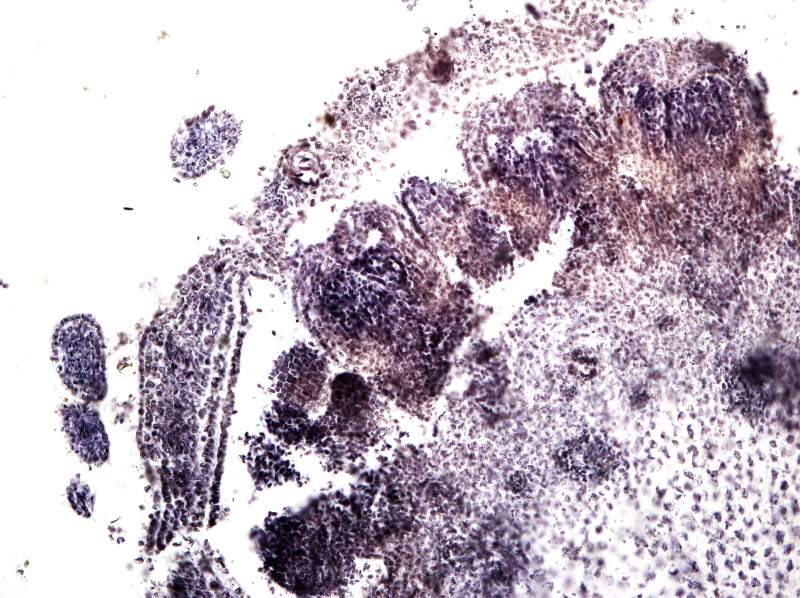

°¥£¬ËùÒÔºËÐļ¼Êõ»¹ÊÇÒª×Ô¼ºÕÆÎÕ²ÅÐÐ PSÓÖ²»ÊÇ×÷¼Ù£¬ÉúÎïѧ¿ÆÍ¼Æ¬µÄ´¦ÀíÓлù±¾µÄ¹æ¶¨£¬ÒªÊÇ˵È˼ÒÊÇPSµÄ£¬È˼ÒÁ˲»Æðµ÷Õûһ϶ԱȶÈÖ®À࣬¿Ï¶¨²»Äܰѿ´µÃ¼ûµÄµ÷ûÓУ¬Ã»¿´¼ûµÄµ÷³öÀ´£¬²»¶Ô½¹µ÷³É¶Ô½¹Êǰɣ¿£¡£¡£¡ÄãÈÃËûÈ¥µ÷£¬ÕâÖÖͼ¶¼¸Ð¾õ¶¼Ã»ÓжԽ¹£¬ÄãÈÃËûµ÷³öËûËùνµÄPSµÄЧ¹û£¬Ç°ÌåÊDz»Äܳ¬¹ýµ÷ÕûµÄ¹æ¶¨¡£²»È»µÄ»°Õâ¸öÕʼá¾ö²»´ò¸øËû¡£ |